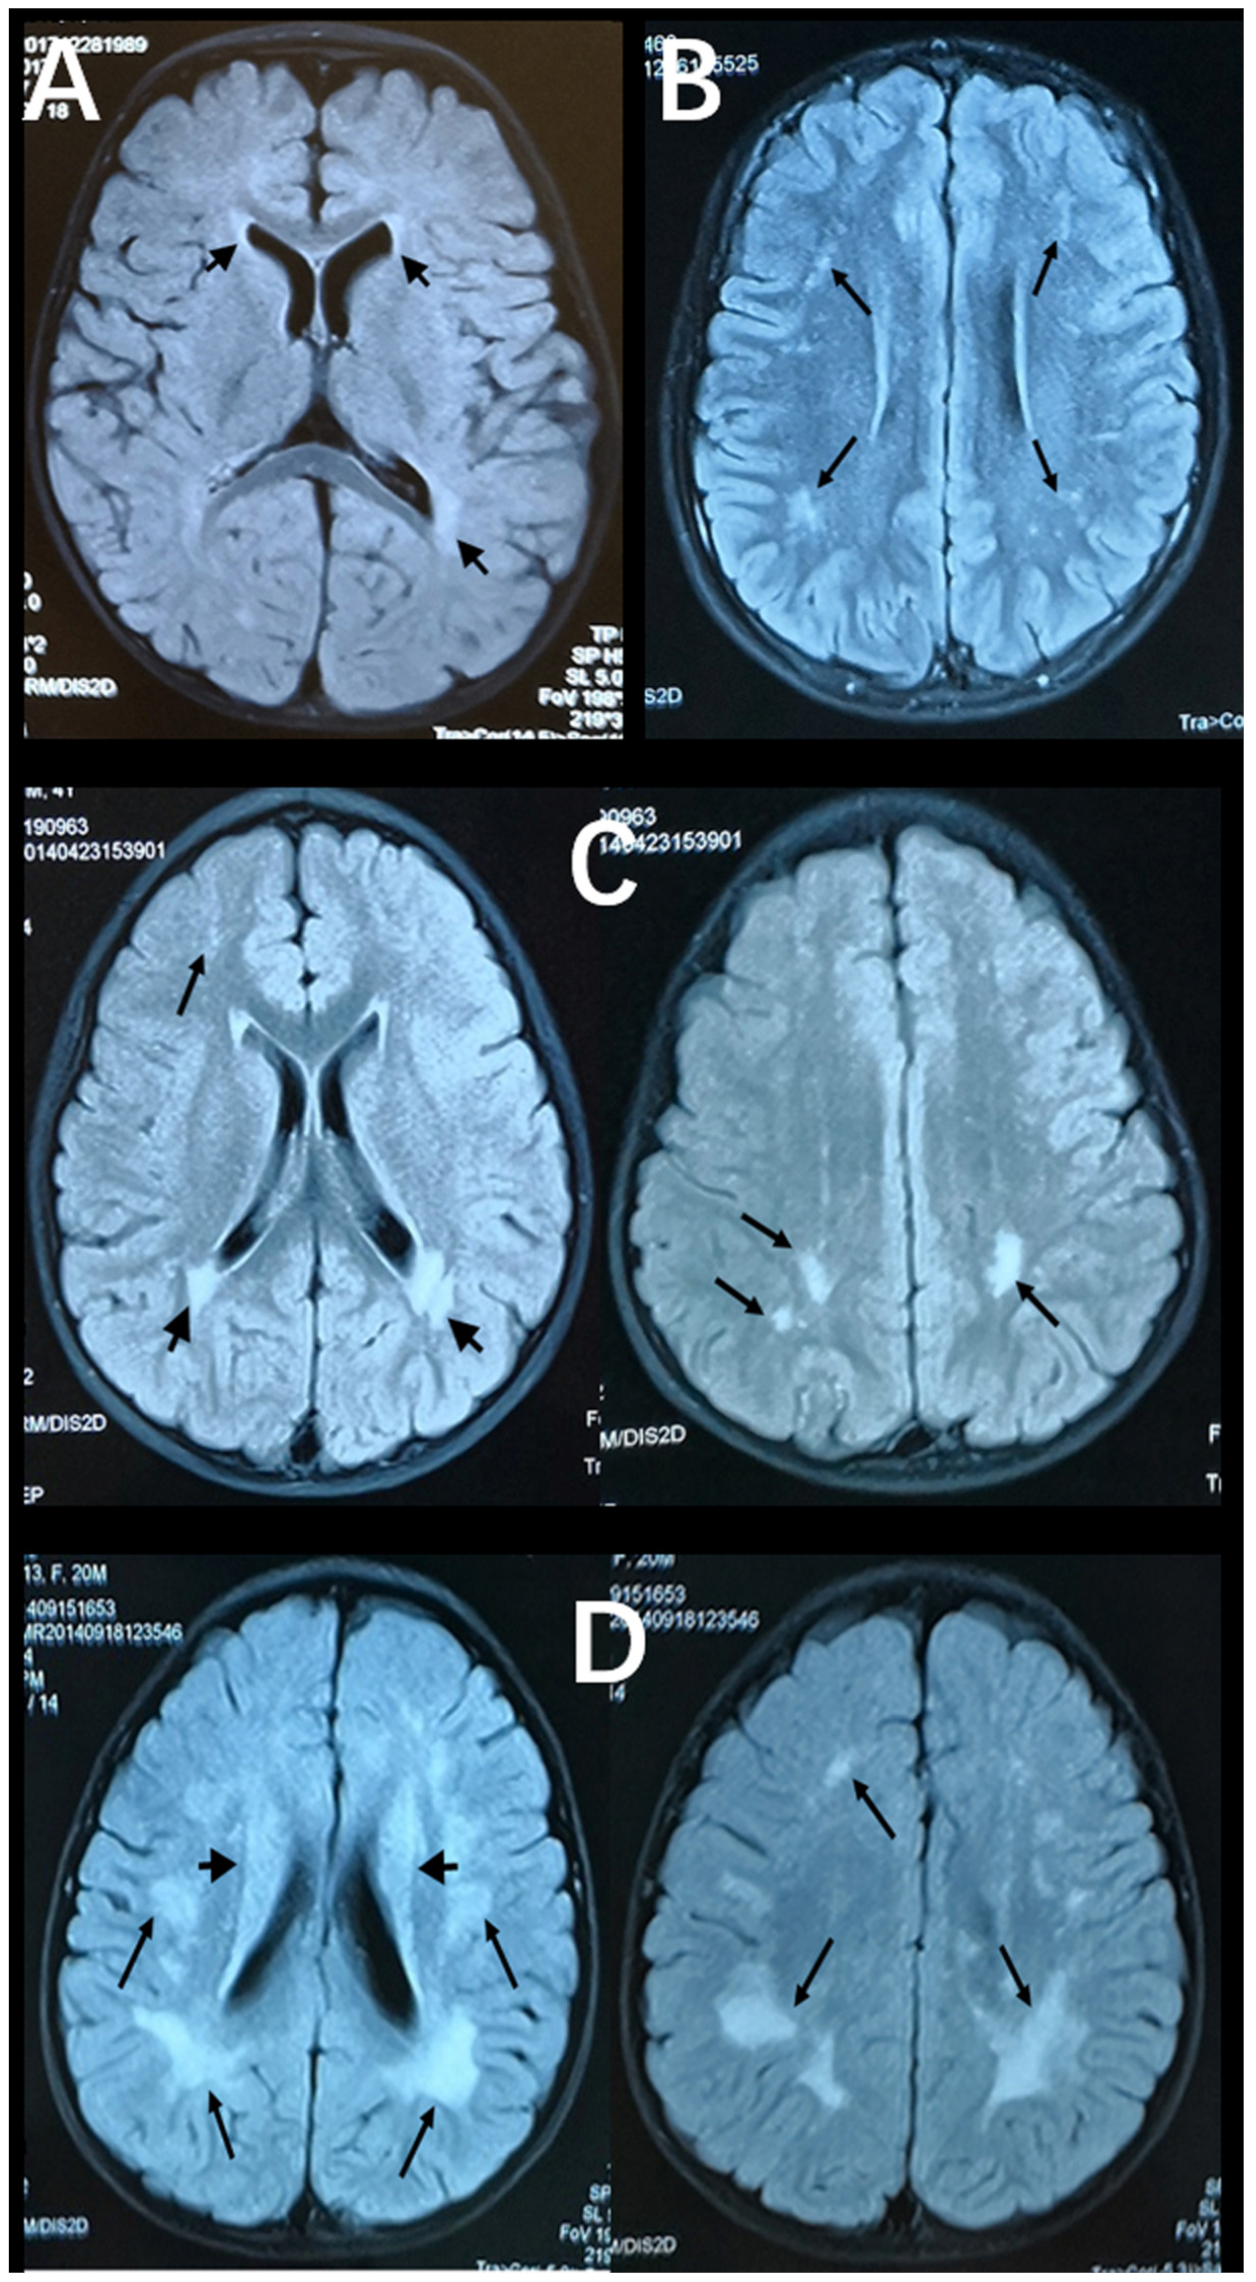

Figure 2 and Figure 3 show representative T2-FLAIR images with annotated Fazekas scores and involved areas. The numbers of participants with Fazekas scores of 1, 2, 3, 4, 5, and 6 were 15, 15, 2, 5, 4, and 2, respectively. PVH was detected in 25 participants and DWMH was detected in 32 participants. PVH and DWMH were detected concurrently in 14 participants. The frontal lobe (31/32) was the most frequently involved area of deep white matter, which was followed by the parietal lobe (22/32) and the occipital lobe (11/32). The temporal lobe (10/32) was the least involved area. Table 3 shows the distributions of Fazekas scores and involved areas.

Figure 2. Axial, T2-FlAIR cerebral MRI scans with annotated Fazekas scores. (A) Multifocal WMLs in periventricular white matter (short black arrows, PVH = 1, Fazekas score = 1). (B) Multifocal WMLs in deep white matter (black arrows) of the frontal and parietal lobes (DWMH = 2, Fazekas score = 2). (C) Extensive WMLs in periventricular white matter (short black arrows) and deep white matter (black arrows) of the frontal and parietal lobes (PVH = 3, DWMH = 2, Fazekas score = 5). (D) Diffuse WMLs in periventricular white matter (short black arrows) and deep white matter (black arrows) of whole brain areas (PVH = 2, DWMH = 3, Fazekas score = 5).